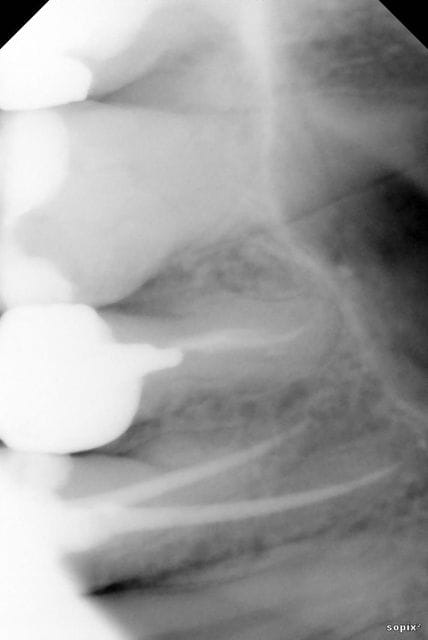

et à chaque fois même réaction, douleur à la percussion sur les dents concernées, dans les 15 j 3 semaines qui suivent, qui cèdent aux antiinflammatoires, et qui reviennent des l’arrêt de ceux ci (je précise que le traitement n'est pas de moi, elle en prend pour son dos). J'ai essayé de retraiter les dents, après mes premiers traitements, de les mettre sous hydroxyde de calcium, rien n'y fait. (j'ai joint la radio de la 14, par soucis informatique j'arrive pas à retrouver les autres, si je met la main dessus je les posterais).

pour la radio, c'est la radio 1 mois après traitement,juste avant que je la désobture donc, les douleurs ont commencé 15 j après le premier traitement, quand elle a arrêté le traitement antiinflammatoire pour son dos.